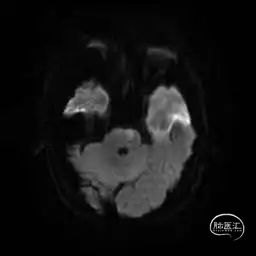

MRI提示小脑缺血性改变。

术后CT:未见明显脑出血,双侧小脑低密度影。

术后9天MRI: